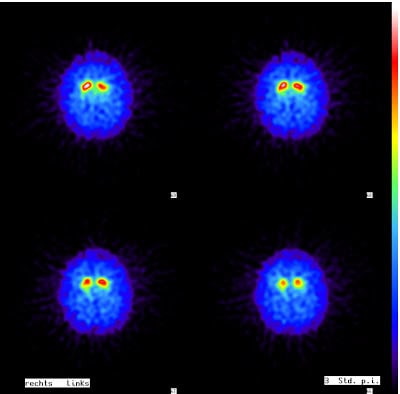

Parkinson-Erkrankungen und Parkinson-Syndrome (z.B. eine Multisystematrophie, MSA) können sehr empfindlich mittels eines DaTScans nachgewiesen werden.

Drei bis sechs Stunden nach Injektion einer schwach radioaktiven Untersuchungssubstanz werden Bilder angefertigt, die in der Regel direkt eindeutige Aussagen liefern.

Normaler DaTScan mit kommaförmiger Darstellung der Striati (= Nn. caudati + Putamina). Der Befund spricht gegen einen M. Parkinson oder ein Parkinson-Syndrom.

Pathologischer DaTScan mit verminderter Darstellung beider Putamina (nur noch Punkte, keine Kommas mehr). Der Befund spricht für einen M. Parkinson oder ein Parkinson-Syndrom, z.B. eine Multisystematrophie.